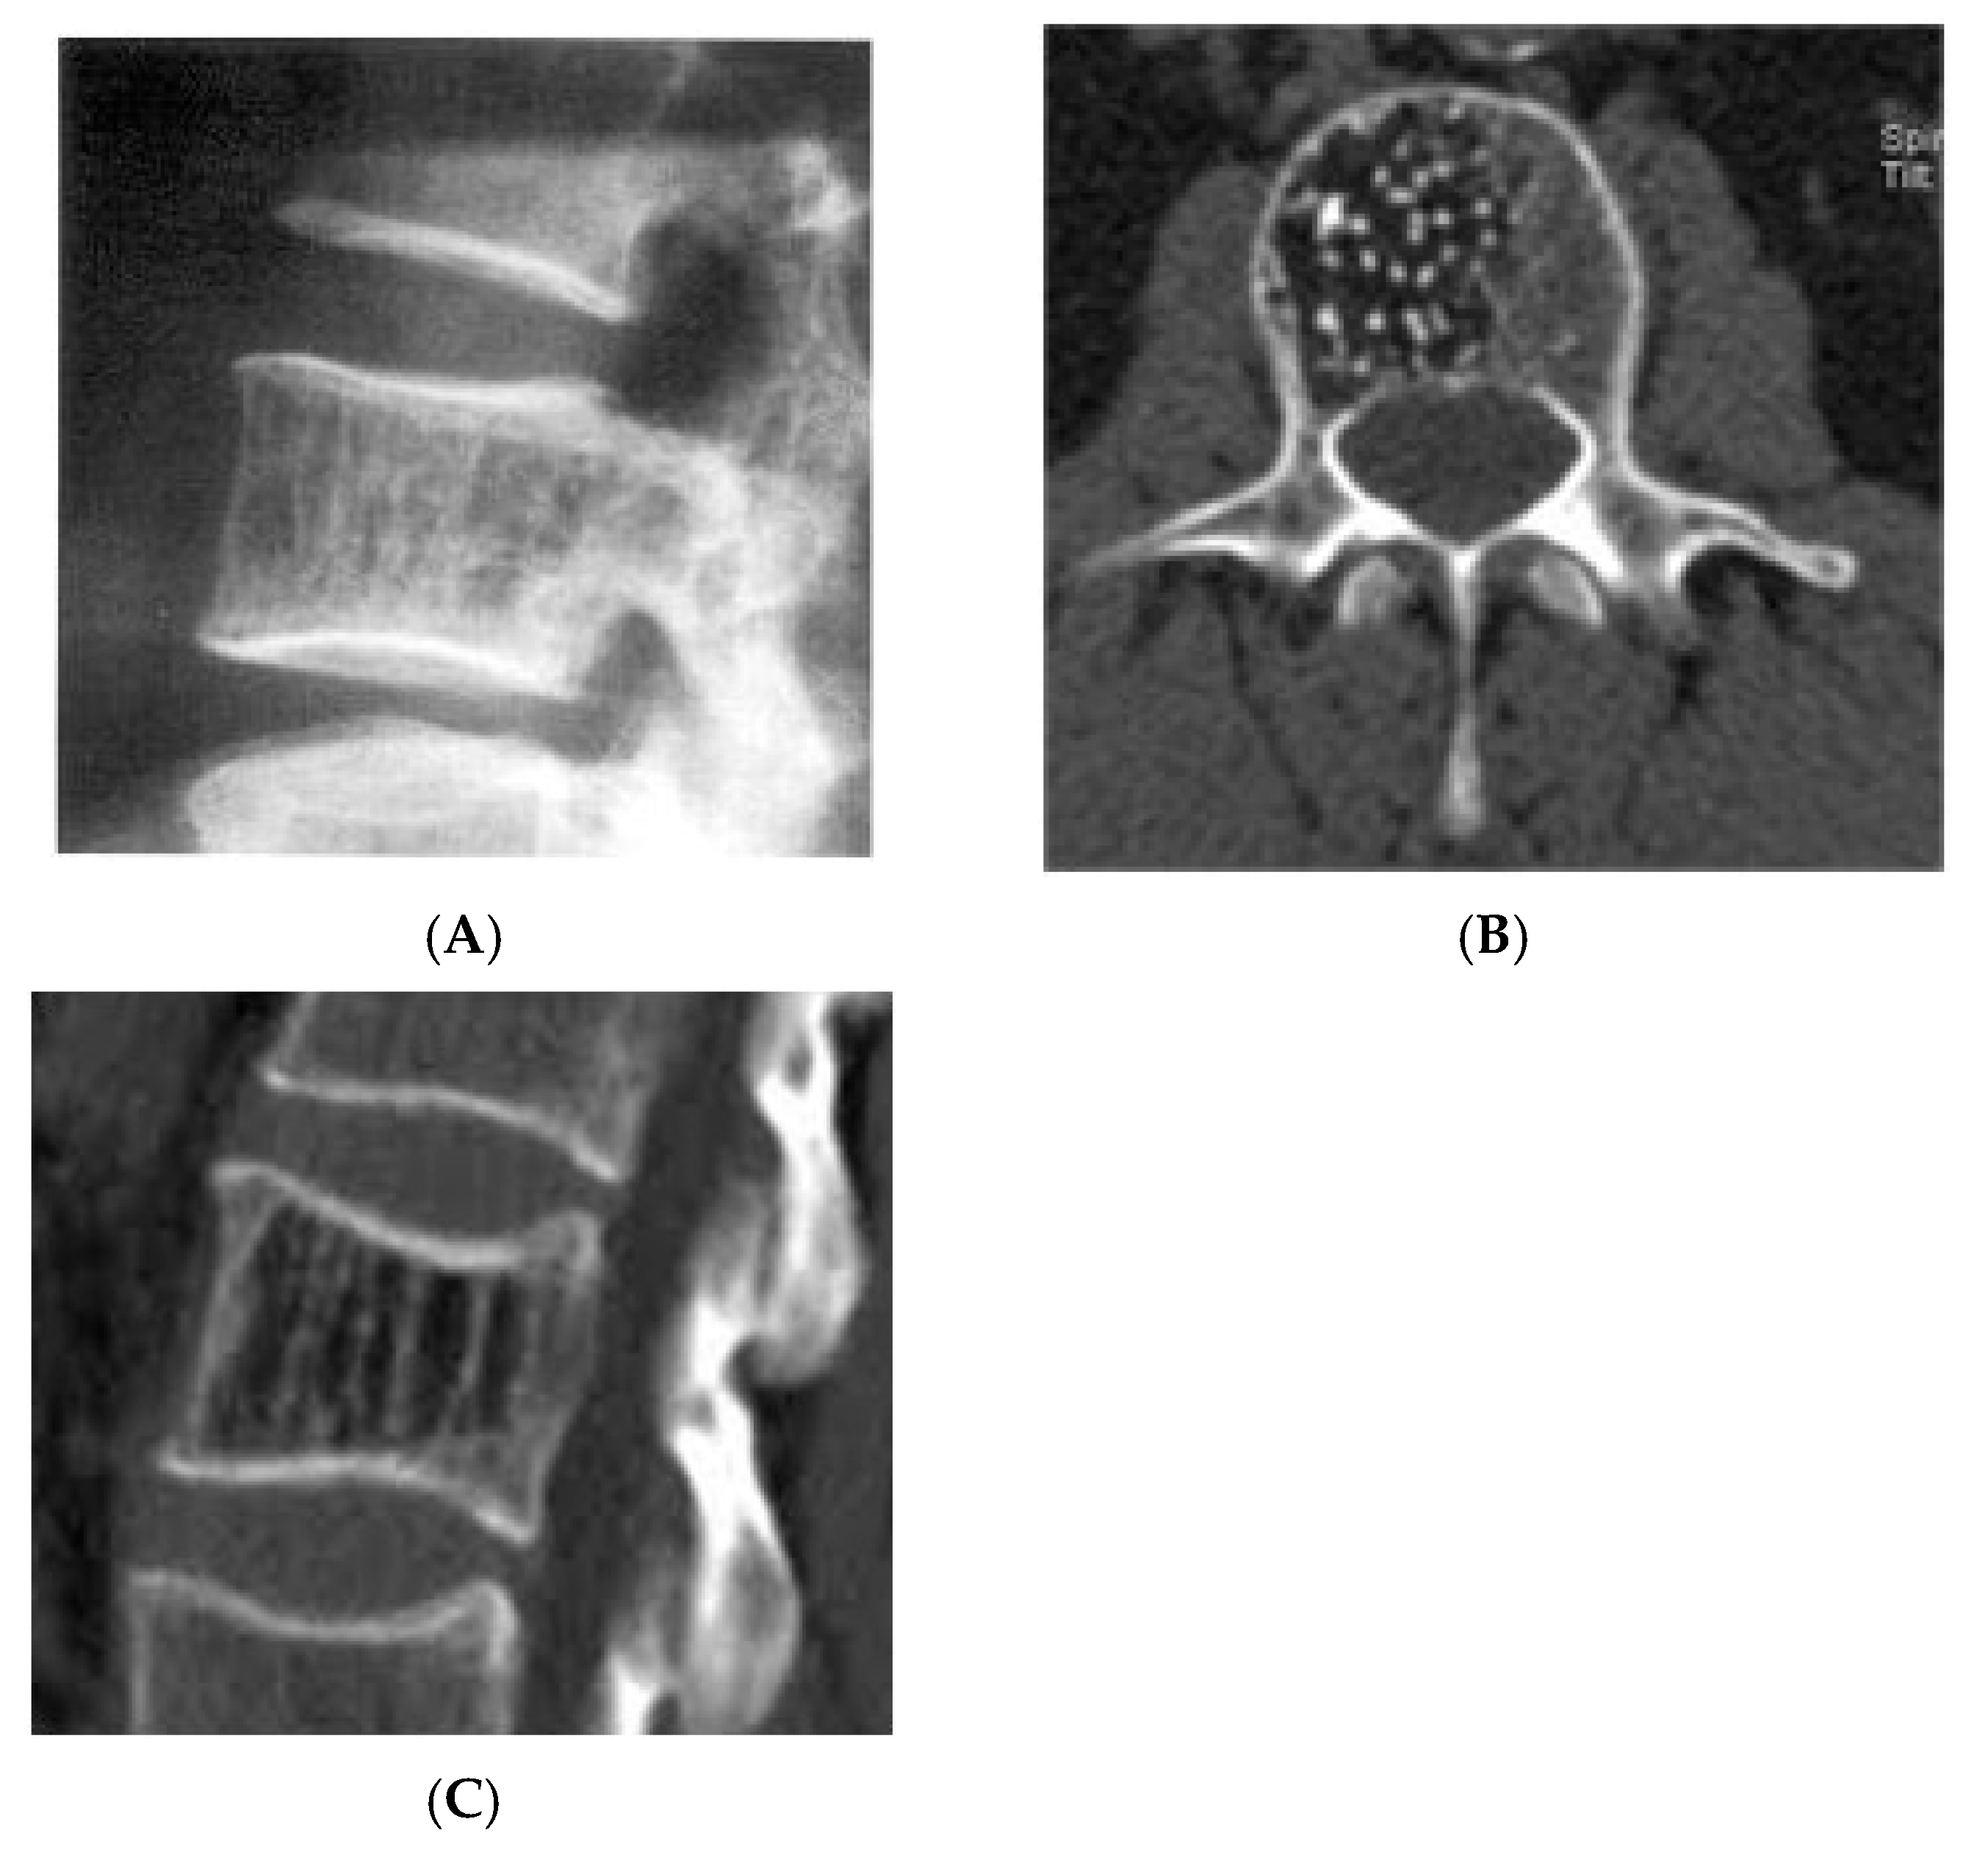

Figure 7.

Vertebral haemangioma. (A) Plain radiograph lateral view demonstrating “corduroy” pattern. (B) Axial CT demonstrating “polka-dot” pattern. (C) Sagittal CT demonstrating “corduroy” pattern.